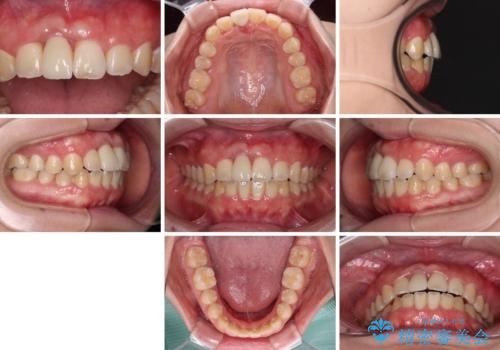

ぶつけてしまった歯は保存が困難な状況であったので抜歯をし、ワイヤー矯正により歯列を整えつつ前歯の突出感を解消することとしました。

矯正治療後にはインプラント補綴治療を行うこととしました。

前歯の補綴治療はインプラントかブリッジかで悩んでいました。

周りの歯にむし歯がないため、インプラントがお勧めとなりますが、事故による骨欠損が大きく、歯肉ラインを整えるのが困難という問題がありました。